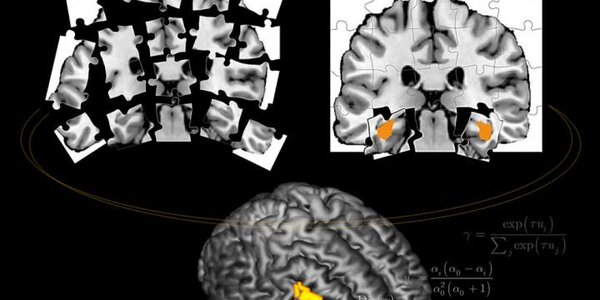

Neuroscientists have discovered brain circuitry for encoding positive and negative learned associations in mice. After finding that two circuits showed opposite activity following fear and reward learning, the researchers proved that this divergent activity causes either avoidance or reward-driven behaviors.  Prior to the new study in Nature, scientists suspected involvement of the circuits ultimately implicated, but were stumped by a seeming paradox. A crossroads of convergent circuits in an emotion hub deep in the brain, the basolateral amygdala, seem to be involved in both fear and…